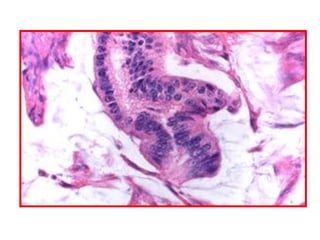

Meningioma

1

2

1) Whorls of round, spindle or oval cells

2) Central capillary with hyalinised wall

Multiple psammoma bodies